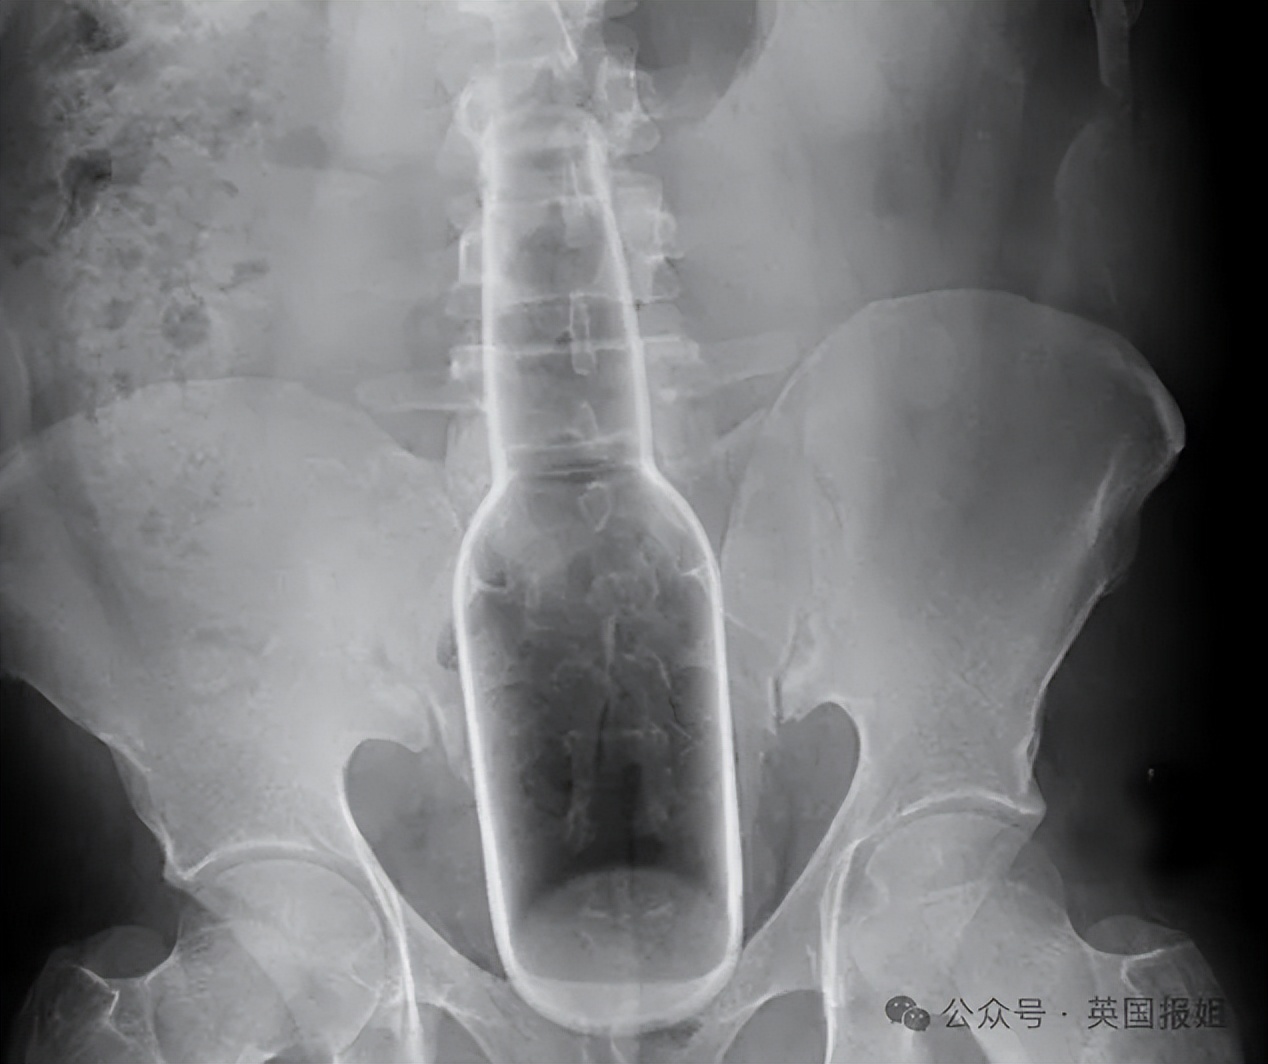

面对这些一问三不知的病人,医生就要给他们做一个全方位的检查,用X光片来帮助他们回忆起病史。这样一来,接诊时间就会被延长,会导致已经有内出血或肠梗阻的患者面临更大风险。

在这份白皮书里就有一个类似病例。这名伊朗病人当时送到急救科时并未主动告知“菊花”被卡,只说自己腹部异常疼痛。

做完X光片后,医生惊讶地发现他直肠里有一大瓶除臭剂,而且异物因为患者的不断收缩,已经跑到消化道了。

最终,经过胃部切开手术急救,这名患者才捡回一条命。